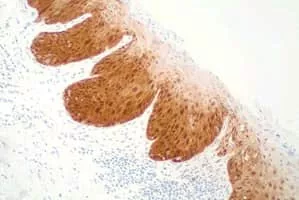

p16 photograph

p16, is a protein that slows cell division by slowing the progression of the cell cycle from the G1 phase to the S phase, thereby acting as a tumor suppressor. It is encoded by the CDKN2A gene.